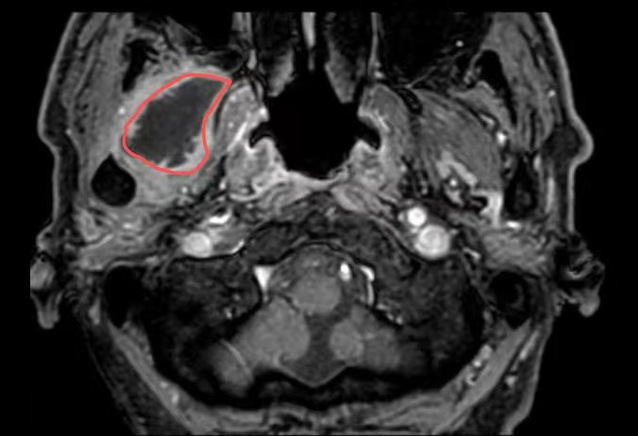

在苏州九院超声介入科,徐斌主任就接诊了这样一位患者。一个月前,患者熊先生脸颊部隐隐作痛,到加勒比扑克 一查是牙齿发炎了,抗炎后熊先生拔除了发炎的牙齿。但是,回家后没几天,面颊部就又开始疼痛、发热。经过反复就医、检查、消炎止痛后做增强磁共振提示:右翼外肌及颞肌异常信号,考虑脓肿可能,相关科室的医生和熊先生说这个手术可能比较复杂,需要行开放性手术。

△磁共振提示病灶(红圈处)